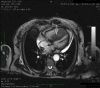

Metastatic spread to the heart from neoplasms is very rare, often silent and rarely gains clinical attention. Usually, it correlates with widespread metastatic disease and is suggestive of a poor prognosis. Most cardiac metastases (CM) are detected following post-mortem studies with only a handful reported antemortemly. Here, we report a case of an asymptomatic cardiac metastasis from esophageal carcinoma and a review of the literature. In late July 2014, a 73-year-old woman diagnosed with locally advanced esophageal squamous cell carcinoma was admitted to our institution. Cardiothoracic metastases were not detected at basal computed tomography (CT) scan. The patient was submitted to concurrent cisplatin and radiotherapy. Just before surgery, a CT scan revealed two metastases in the right ventricle and in the interventricular septum. Transthoracic echocardiography and an endomyocardial biopsy confirmed the diagnosis of squamous cell carcinoma from the esophageal origin. In February 2015, chemotherapy was started, but after two courses of gemcitabine, a pulmonary embolism and then a congestive heart failure caused death of the patient on April 2015. Reviewing the literature, 14 cases with an antemortem diagnosis of CM from esophageal cancer were reported. Our patient should be the fifteenth case with an uncommon presentation without symptoms or signs in the diagnosis. Our case highlights that patients should be evaluated using echocardiography for CM, even if asymptomatic.